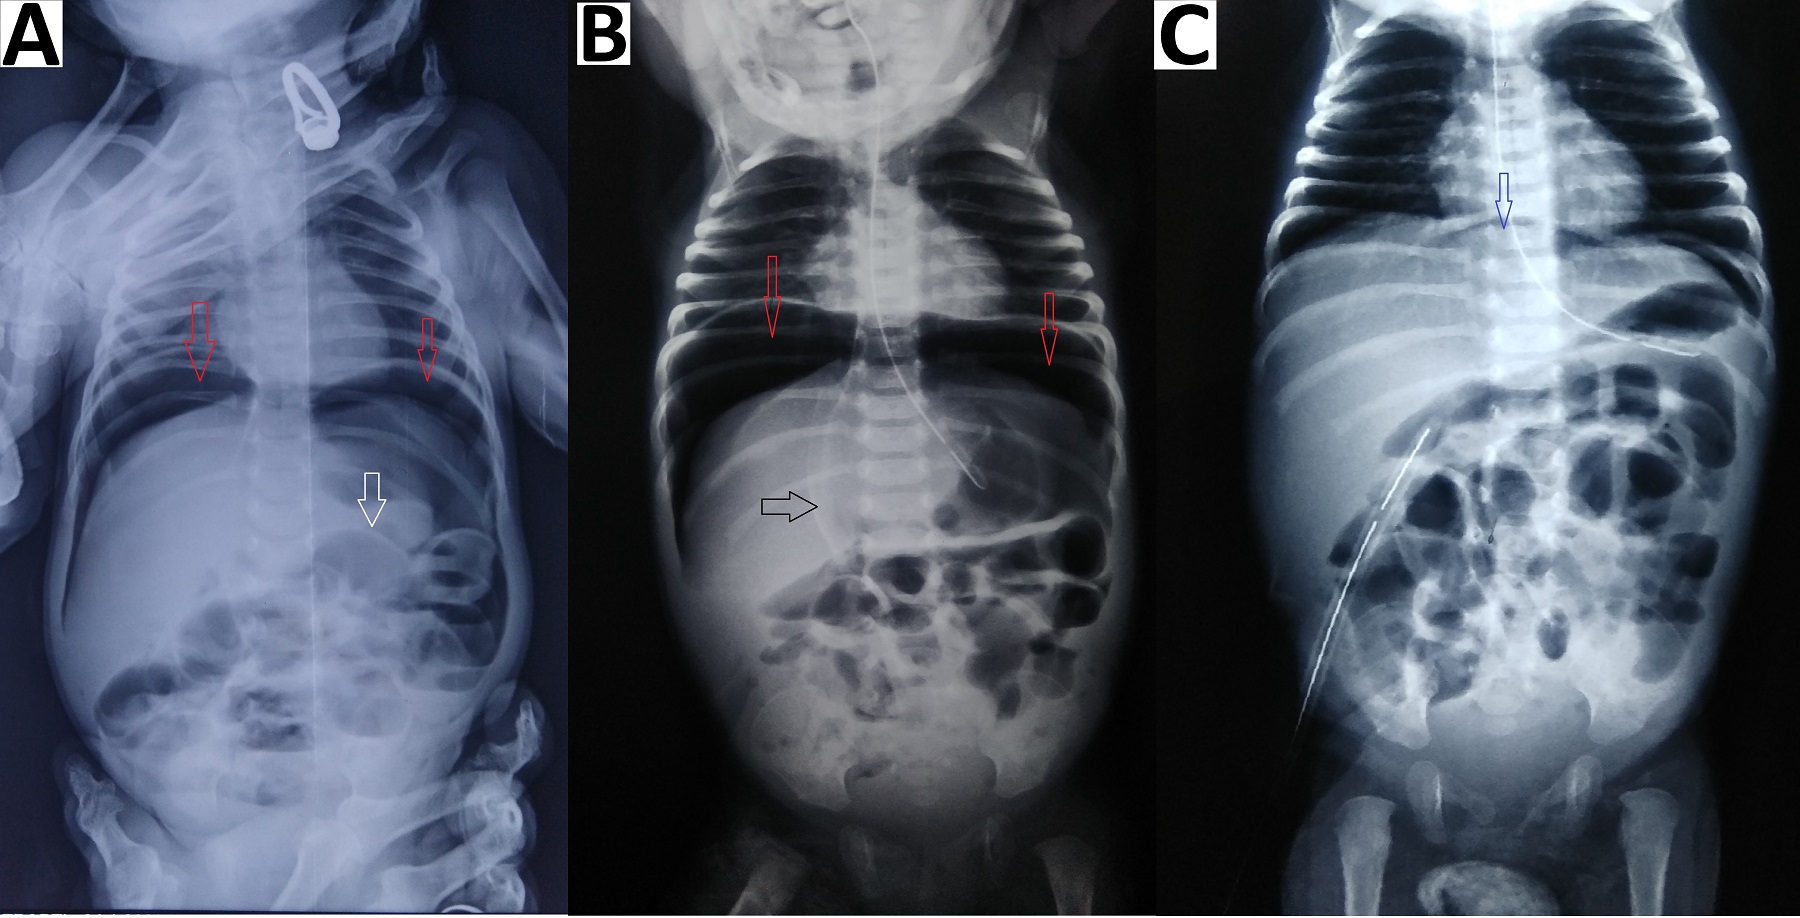

Figure 2

Abdominal radiographs (erect) (A) showing gas under the diaphragm (red arrows), Rigler sign (white arrow); supine image (B) showing pneumoperitoneum (red arrows), outlining of falciparum ligament (black arrow); erect image (C) showing resolution of pneumoperitoneum (blue arrow) with abdominal drain in-situ.

Pneumoperitoneum with air under both the domes of the diaphragm was seen in all 4 patients on erect abdominal radiographs (Fig. 1)(Fig. 2)(Fig. 3)(Fig. 4). There was an absence of free fluid in the peritoneal cavity evident by the absence of air-fluid level in the peritoneal (abdominal) cavity i.e. outside bowel loops in all the patients. Dilated small bowel loops were seen in 3 out of 4 patients. Rigler sign or double-wall sign was present in 3 patients. Radiographic evidence of pneumothorax (simultaneously present with pneumoperitoneum) was seen in 1 patient (Fig. 4). Pneumoscrotum was appreciated in 2 patients (Fig. 3)(Fig. 4).

Pneumoperitoneum in a neonate is classically due to GI perforation and necrotizing enterocolitis (NEC).[3], [4] Pneumoperitoneum is usually diagnosed by an erect abdominal radiograph showing free air under the domes of the diaphragm. In the neonates the other radiographic signs include, (a) rounded or oval lucency over the upper abdomen in the supine position, (b) increased lucency i.e. triangular or a semilunar collection of air anterior to the abdominal viscera or above the liver in lateral decubitus position, (c) large volume of free air may give rise to the football sign, where the air outlines the whole of the peritoneal cavity and under the surface of the diaphragm, (d) the lacing of the football i.e. outlining of falciparum ligament of the liver against the radiolucency of free abdominal air on supine view [4], [5], [6] (e) Rigler sign or double-wall sign is free gas on both sides of the bowel wall,[4], [5] (f) pneumoscrotum has been explained due to presence of patent processus vaginalis and passage of air from the peritoneal cavity into the scrotum.[3], [5], [6]